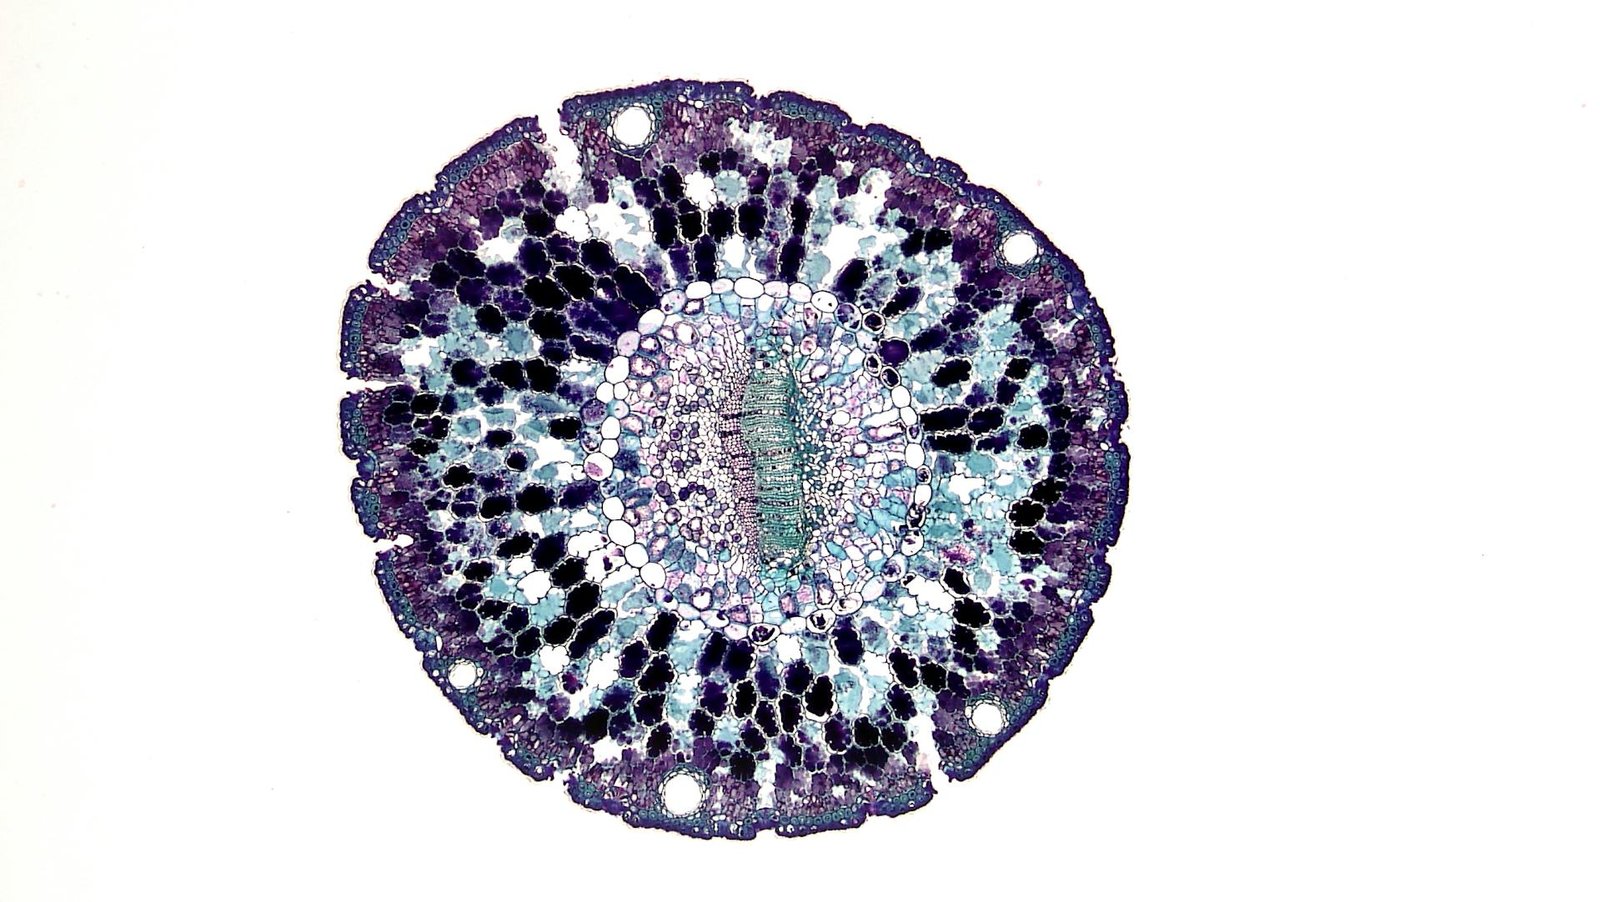

Mesenchymal stem cells (MSCs) are a type of multipotent adult stem cell first discovered in bone marrow but also present in adipose tissue, umbilical cord, placenta, dental pulp, and other sources.

- MSCs can self-renew and differentiate into osteoblasts (bone cells), chondrocytes (cartilage cells), and adipocytes (fat cells).

- They express specific surface markers (positive for CD73, CD90, CD105; negative for CD34, CD45).

- They can be expanded in culture and retain therapeutic properties. In simple language, it means that we can extract few MSC cells from certain tissues like fat cells (most readily accessible source in patients), and then multiply them in labs to increase their quantity to manage health conditions.